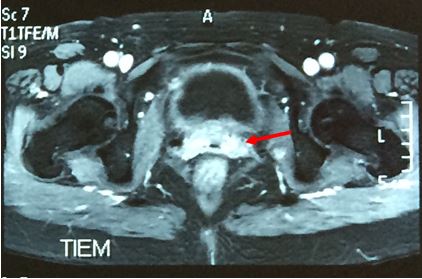

Chụp PET/CT:

-          Khối u vùng cổ tử cung (phía sau bàng quang) kích thước 5,7x6,1x7,6 cm tăng hấp thu FDG, max SUV = 10,88

-          Hai hạch chậu phải KT 2,2 cm tăng hấp thu FDG, max SUV = 6,81 và 2 cm tăng hấp thu FDG, max SUV 8,86

Hình 1. Hình ảnh PET/CT toàn thân: Khối u cổ tử cung kích thước lớn (mũi tên đỏ), hạch chậu phải (mũi tên vàng)

Chẩn đoán:Ung thư biểu mô tế bào vảy cổ tử cung T2N2M0, Giai đoạn: IIIb